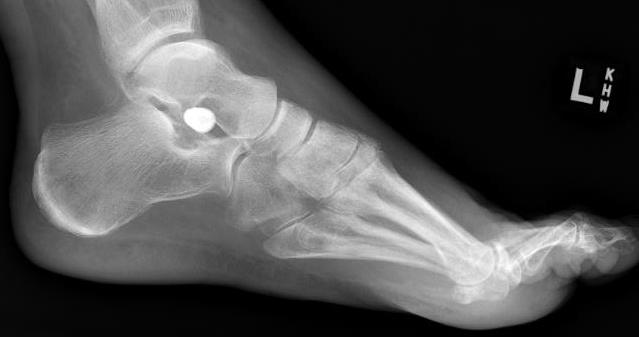

Subtalar arthroeresis

implantimplantimplant

Concept

Sinus tarsi implants limit excessive pronation

Endosinotarsal - implant in the sinus tarsi

Exosinotarsal - screw external to the sinus tarsi